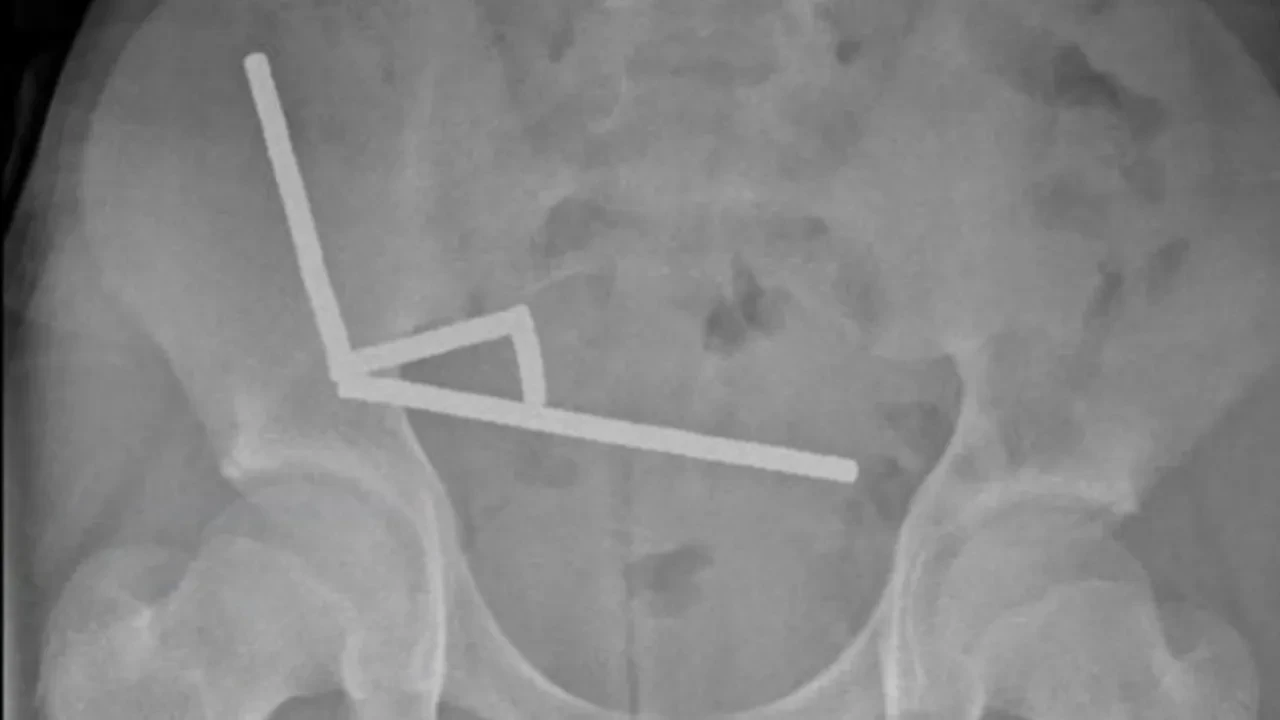

Tauranga Hastanesi'ndeki cerrahlar, New Zealand Medical Journal'da yayımlanan makalelerinde vakayı "endişe verici" olarak nitelendirdi. Çocuğun yaklaşık bir hafta önce Çin merkezli alışveriş platformu Temu'dan sipariş ettiği 80 ila 100 adet 5x2 mm boyutlarındaki yüksek güçlü mıknatısı yuttuğunu itiraf ettiği belirtildi.

Neodimyum, mevcut en güçlü mıknatıslardan bazılarının yapımında kullanılan nadir bir toprak metal elementi olup internetten kolaylıkla satın alınabiliyor. Uzmanlar, yutulduklarında bu tür mıknatısların bağırsaklarda birbirine yapışarak vücudun iki kısmı arasında anormal bağlantılar veya bağırsaklarda deliklere neden olabileceğini belirtiyor.

Mıknatısların çok fazla hasara yol açabileceği, ameliyat gerektirebileceği ve hatta ölüme bile neden olabileceği de özellikle vurgulandı.